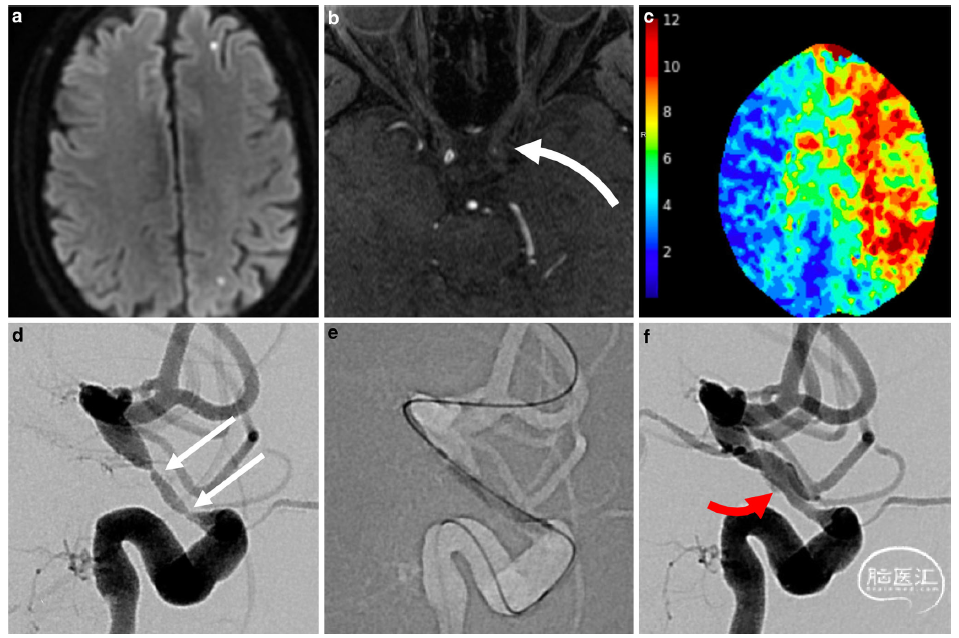

图1.巨细胞动脉炎伴左侧ACA-MCA分水岭缺血的DWI MRI颅内表现(a)。MR血管造影显示LICA床突上段高度狭窄(白色弯曲箭头,b)。CT灌注显示整个左半球存在实质缺血风险,如Tmax图(c)所示,提示需紧急血管内治疗(第1次治疗)。治疗前LICA造影侧位片显示2个严重的狭窄部位(d,白色箭头),采用球囊血管成形术治疗(e)。治疗后血管造影结果(f)显示血流通过时间明显改善,眼动脉和后交通动脉的顺行血流恢复。仔细检查图像发现一处<1cm的非血流限制性小夹层(红色箭头)。

血管内治疗过程中,使用Cook Shuttle 6F鞘管或Benchmark 0.071英寸导引导管支撑的同轴导引导管和Gateway球囊系统(Stryker Neurovascular, Kalamazoo, MI, USA)逐渐扩张(每15-30秒增加1atm)进行经皮腔内血管成形术(percutaneous transluminal angioplasty, PTA)至6atm。血管造影显示狭窄<50%即被视为技术成功。在每次血管内治疗中,在PTA后进行延迟(15 min)血管造影以确认无夹层和急性再狭窄。在LICA首次PTA后发生了一处小的非血流限制性夹层(图1f);基于该并发症及支架植入术所带来的额外风险,在后续治疗中推迟PTA后支架植入术。